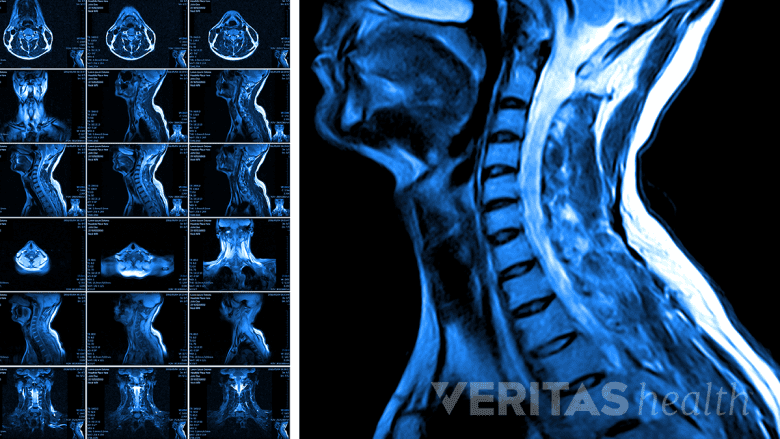

MRI scans are used to confirm the diagnosis of cervical stenosis with myelopathy.

- Imaging study. If cervical stenosis with myelopathy is suspected based on medical history and physical exam, the spinal cord impingement within the narrowed canal can usually be confirmed with an MRI scan or CT scan with myelogram. Flexion/extension lateral cervical spine x-rays are also useful to check for abnormal motion and instability, which can also be present with cervical myelopathy and would affect treatment decisions.